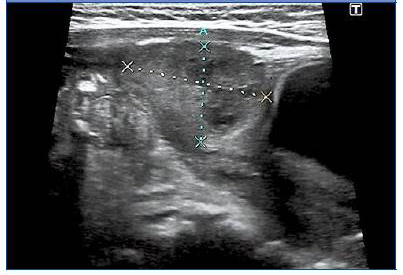

A las 24 horas de ingreso se realizó una ecografía de abdomen, donde se visualiza adyacente a la zona superior de la vejiga hacia el ombligo una colección heterogénea de 5,5 × 2,5 × 2,4 cm (Fig. 2), con diagnóstico de probable quiste de uraco infectado. Posteriormente se aísla en cultivo de exudado Staphycoccus aureus, manteniendo el tratamiento con cloxacilina con buena evolución, desaparición de los signos inflamatorios y de la secreción purulenta. Es dada de alta a los seis días de ingreso, con seguimiento por Cirugía Pediátrica.